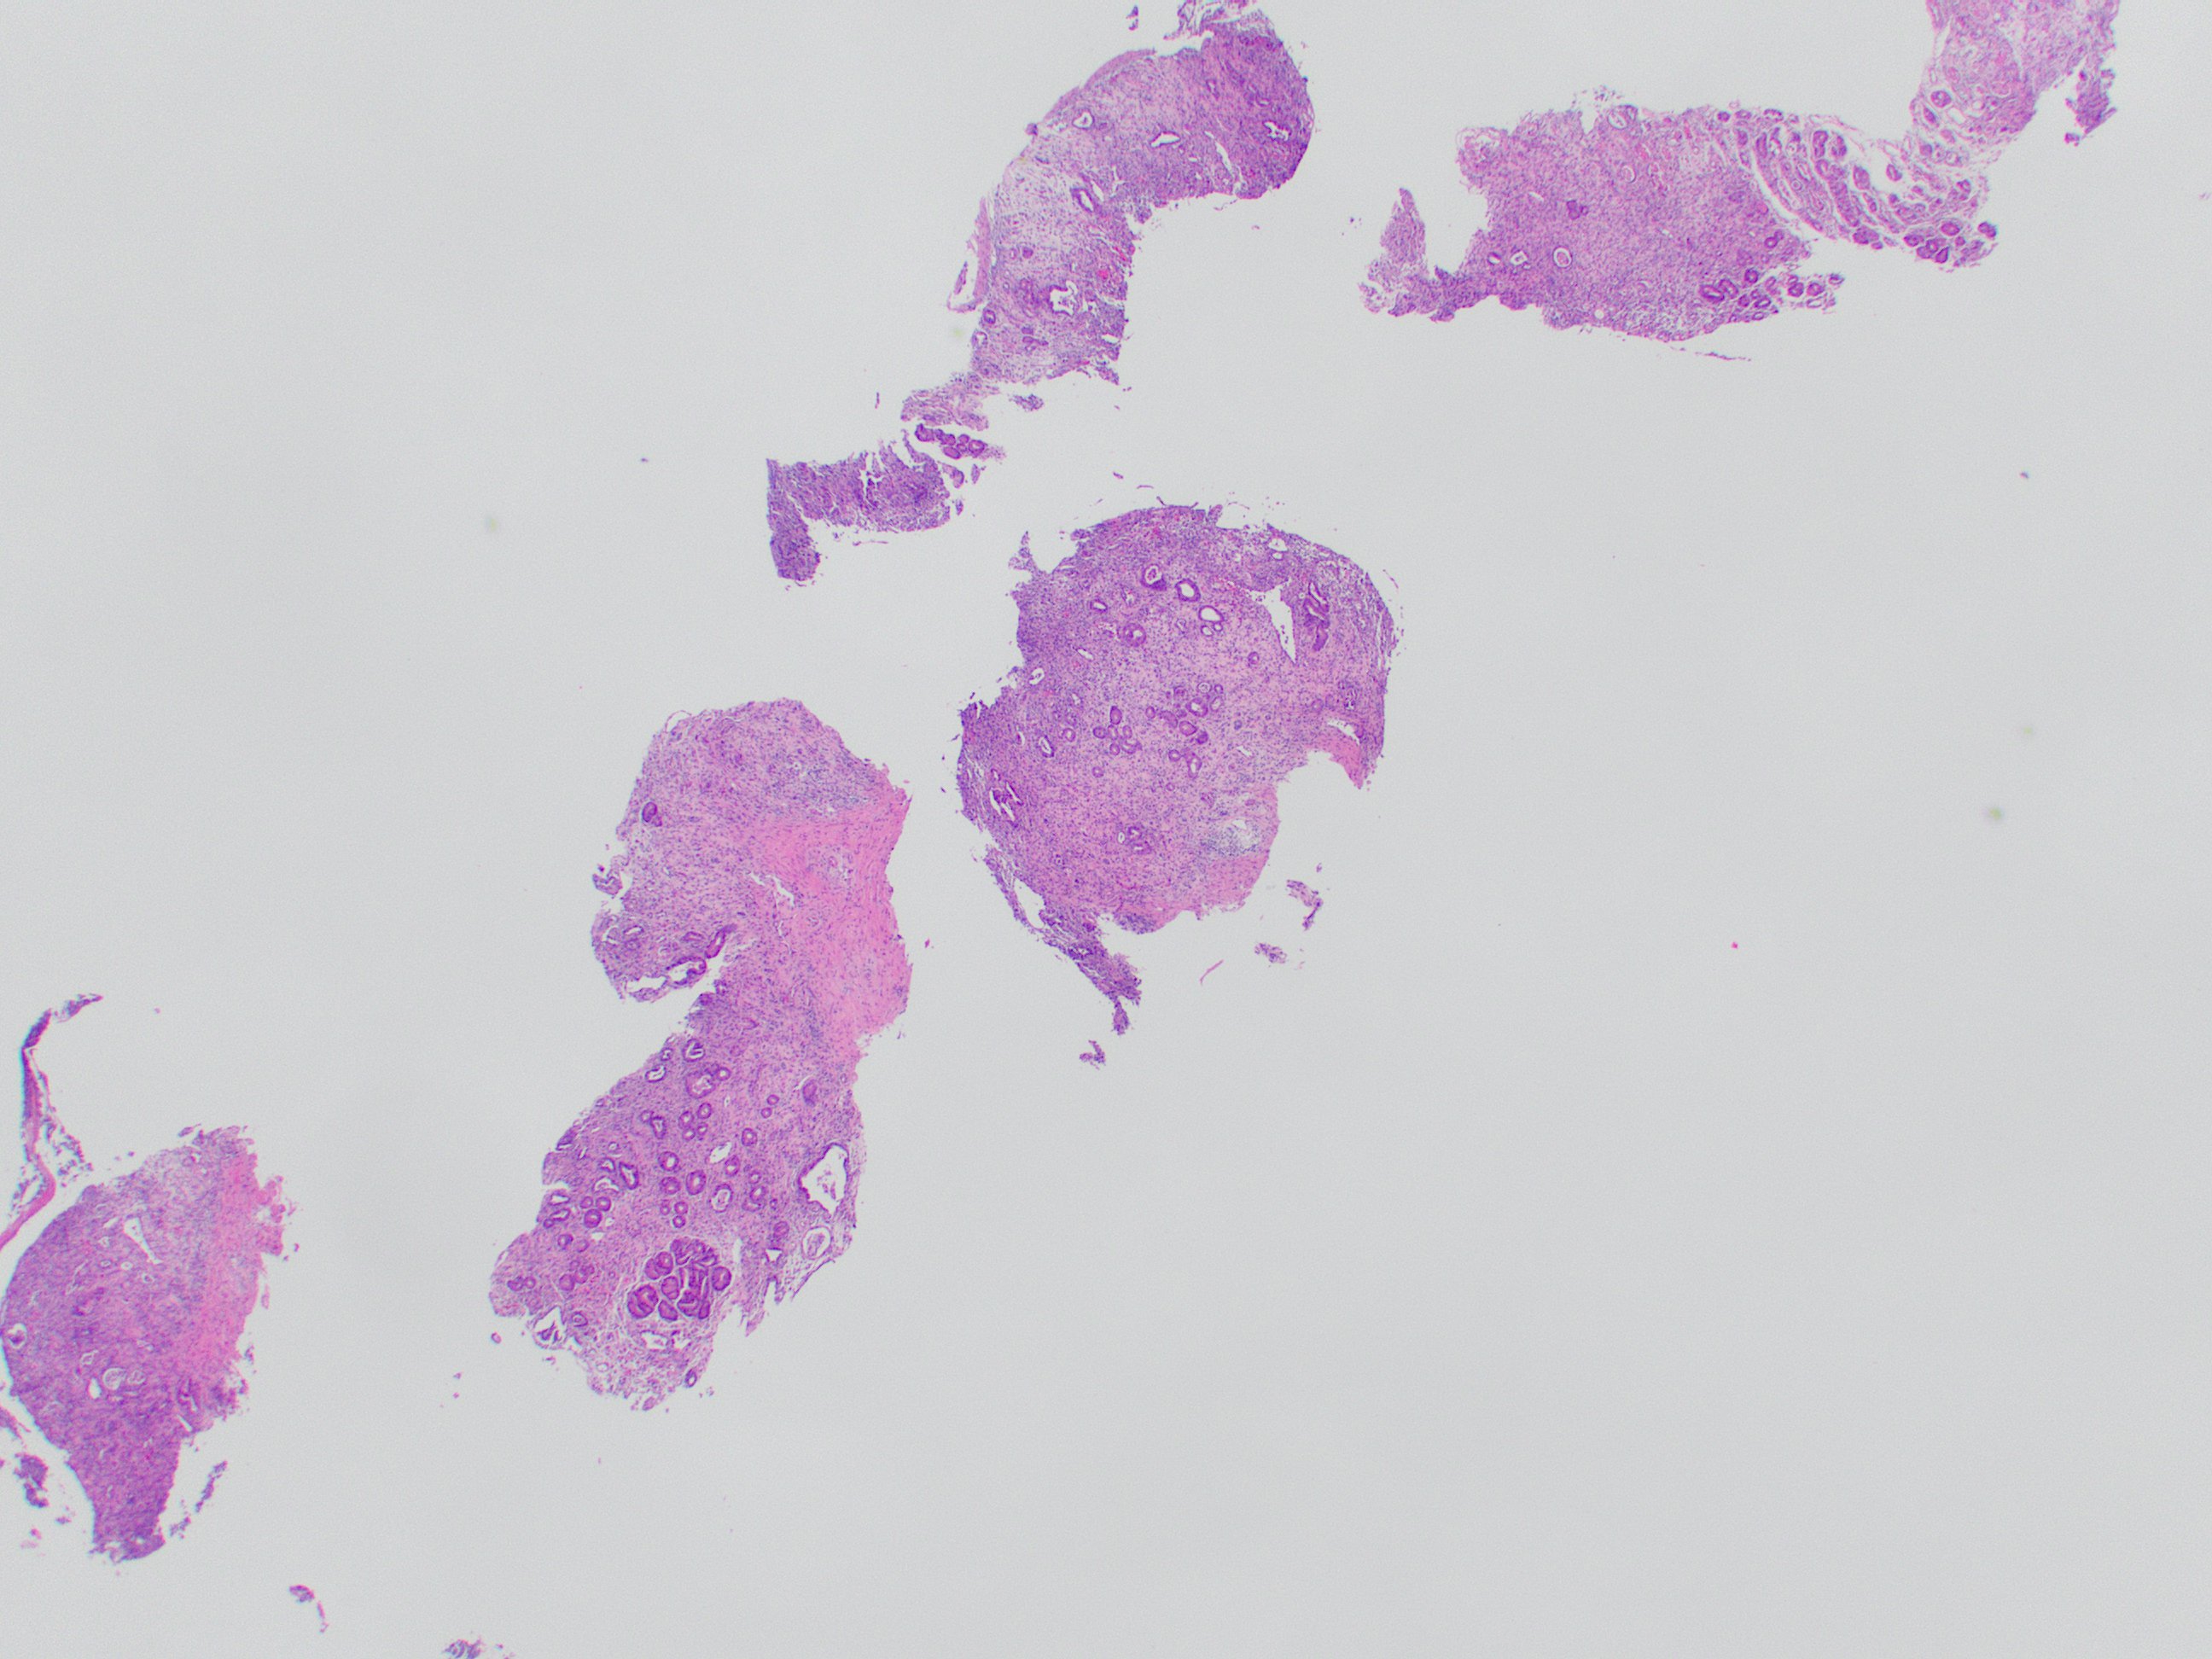

That covers the basics! Here is a direct side-by-side before and after editing in GIMP:

That covers the basics! Here is a direct side-by-side before and after editing in GIMP: